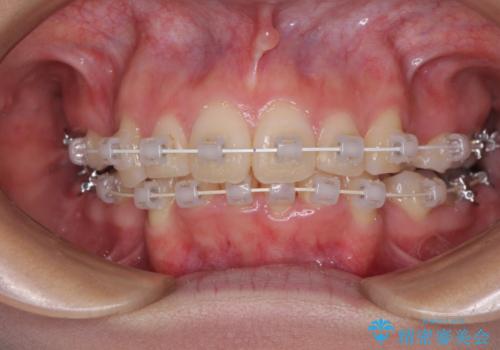

デコボコで飛び出した前歯 ワイヤー装置による抜歯矯正

- 審美装置

- 2年2ヶ月

矯正治療前の咬み合わせで、前歯がすり減ってしまい、歯列が整ったときに先端がガタガタになってしまったため、矯正治療後に形態修正を行いました。